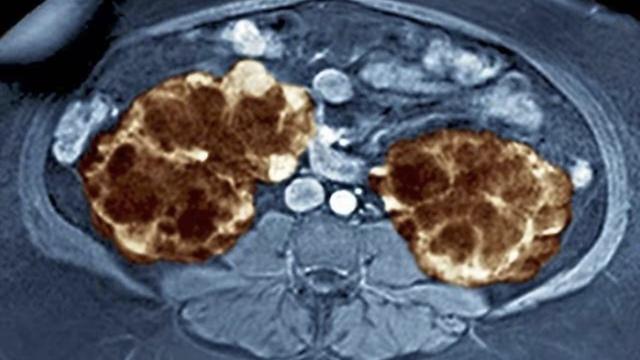

多囊肾,标准叫法为多囊肾病(英文简称PKD),是一种遗传性的慢性肾脏疾病。症状一般表现为双侧的肾脏内存有大小不一的呈葡萄样结构的囊肿,偶尔也有单侧肾脏患上的情况,囊中内充满液体(一般为尿液),这些囊肿不断地增加最终导致肾脏的增大、变形。

增大增多的肾脏囊肿会影响到肾脏,把肾脏撑大,会引起患者腹部饱胀甚至胀痛,严重者还可以隔着肚皮碰到自己的肾脏,会发现肾脏表面呈结节状,质地很硬。